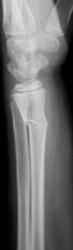

Снят гипс.